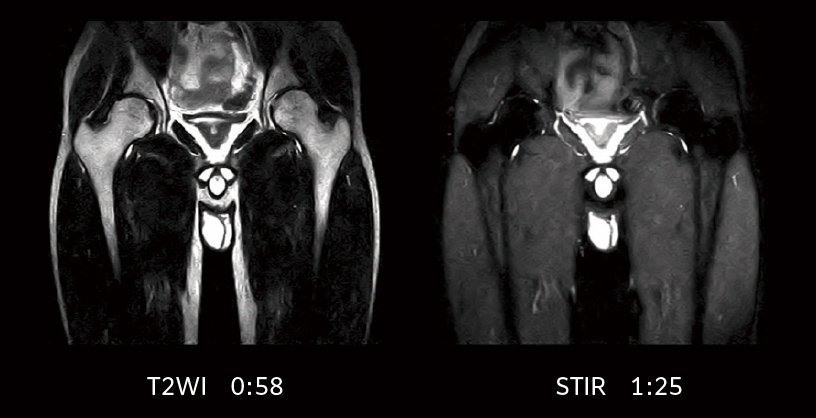

IP-RAPID is a fast scanning technology that reduces scan time while maintaining image quality by optimizing undersampling and iterative reconstruction. It can be used in conjunction with various functions and over a wide range of anatomical regions.